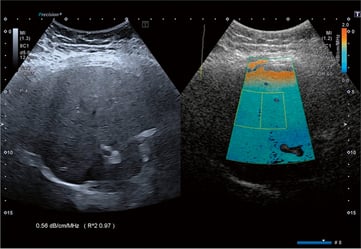

El Coeficiente de Atenuación Ultrasónica (QAI) permite cuantificar el contenido graso hepático.

¿Qué mide?

La atenuación del haz ultrasónico al atravesar el hígado.

La grasa incrementa dicha atenuación.

Resultados

- Expresados en dB/cm/MHz.

Enfoque combinado: el verdadero valor clínico

La combinación de QAI + Shear Wave constituye el enfoque más completo:

| QAI | Esteatosis | Cantidad de grasa |

| Shear Wave | Fibrosis | Rigidez / daño estructural |